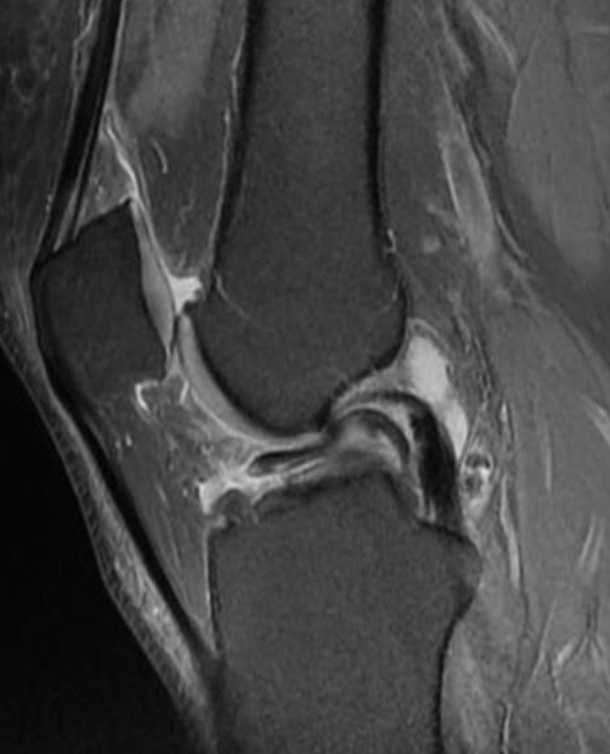

Degenerative meniscus tears typically result from the natural aging process and wear and tear on the knee joint over time. They are often associated with gradual degeneration and weakening of the meniscus. These tears tend to occur in older individuals, typically over the age of 40, and are more commonly seen in the absence of a specific injury or trauma. They develop gradually over time due to the repetitive stress placed on the knee joint. Degenerative meniscus tears may not cause immediate severe pain or functional limitations. But they can result in chronic knee pain, swelling, stiffness, and occasional mechanical symptoms such as locking or catching sensations in the knee joint.

Acute meniscus tears are typically caused by a sudden, forceful twisting or rotation of the knee joint, often associated with a specific injury or trauma. They can occur during activities such as sports or accidents that place sudden, excessive stress on the knee.

They are characterized by an immediate onset of symptoms following the traumatic event. They often cause severe pain, swelling, and functional limitations. Patients may experience a "pop" sensation at the time of injury and have difficulty bearing weight on the affected leg. Mechanical symptoms such as catching or locking of the knee may also be present.